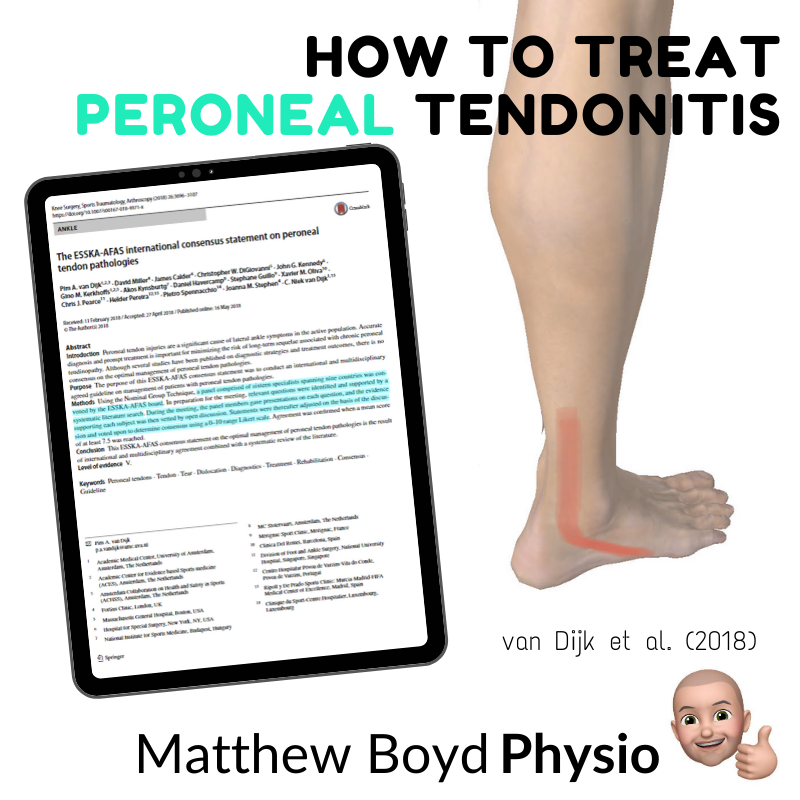

How to Treat Peroneal Tendonitis Matthew Boyd Physio